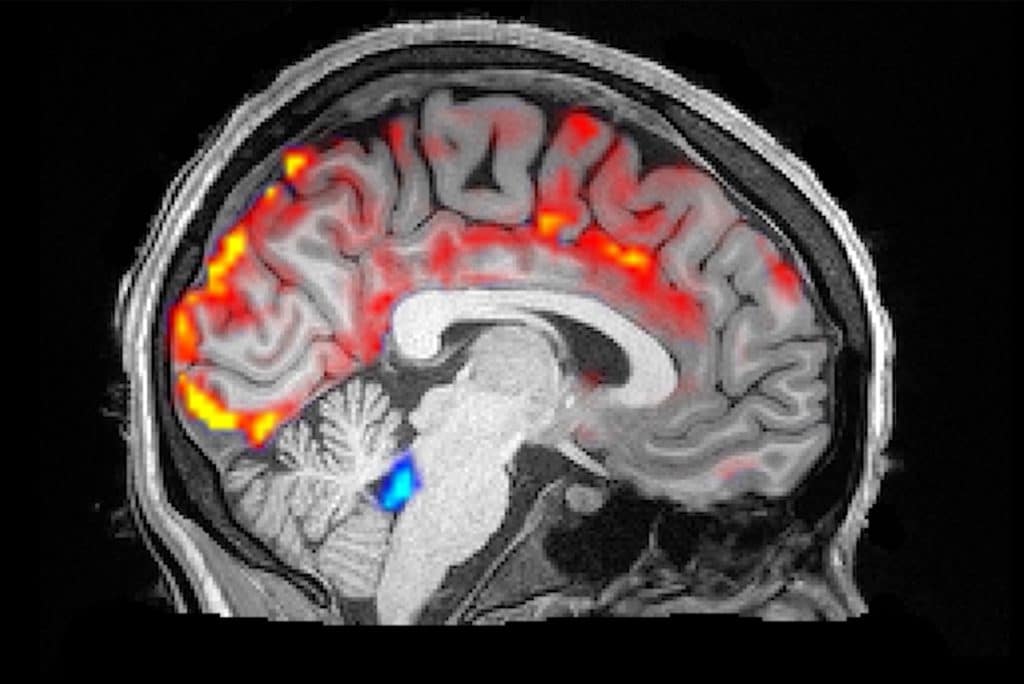

人脑的功能对我们来说仍然是一个很大的谜,我们对它的工作原理知之甚少。2012年,科学家们取得了重大突破,他们发现了glymphatic系统,该系统负责在深度睡眠周期用脑脊液冲洗大脑,清除大脑中的有毒废物。

这种glymphatic系统的不正常工作被认为会影响人体的神经系统疾病,如阿尔茨海默症。但要详细研究这些效应,还需要复杂的核磁共振仪器。为了简化核磁共振扫描过程,美国陆军奖励了莱斯大学、休斯顿卫理公会和贝勒医学院的研究人员,开发了一种可在睡眠时监测和调节大脑液体流动的便携式便帽。